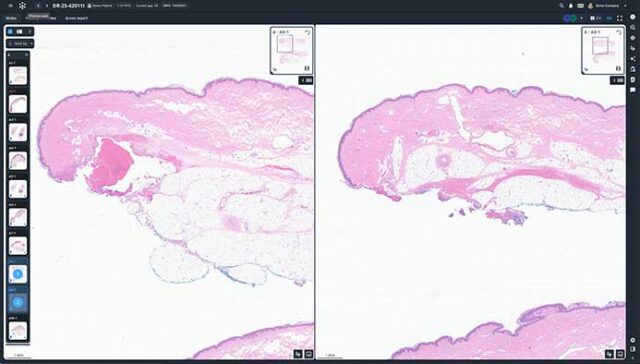

Built with pathologists to deliver an ultrafast cloud-based viewer, flexible worklist, integrated workflows, and state-of-the-art AI.

Techcyte Fusion: The unified anatomic and clinical pathology AI platform

What to expect from the Techcyte platform